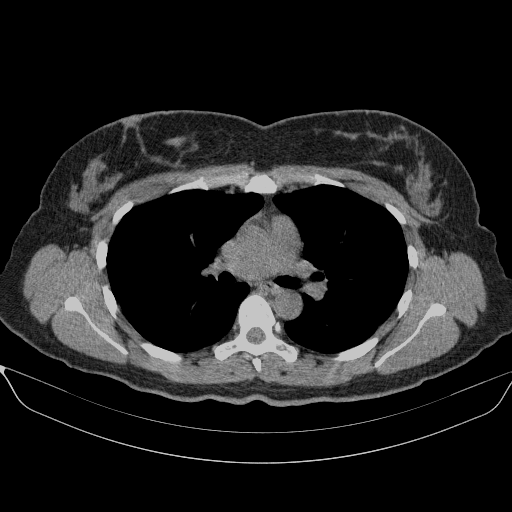

Reconstructed NATIVE CT scan (cycle consistency)

Full window (WL 1023.5, WW 4095 β†’ Low βˆ’1024, High +3071)

Lung window (WL -600, WW 1500 β†’ Low βˆ’1350, High +150)

Mediastinum window (WL 40, WW 400 β†’ Low βˆ’160, High +240)